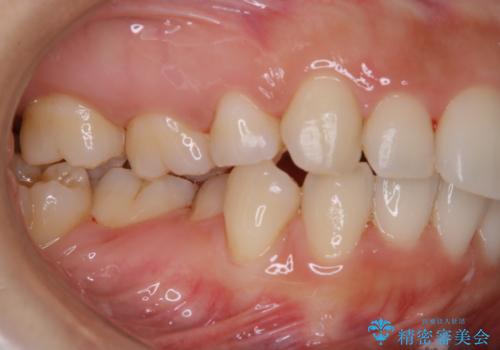

- しばらく来院できなかったため、全体的にチェックとクリーニング希望でした。PMTC60分コースを行いました。

歯にステイン(着色)や歯石などが付着していると、汚れなのか虫歯なのかの判別が分かりにくく、正確な診断ができないことがあります。

そのため、定期的に専門的な機械や材料を使用したクリーニング(PMTC)をすることで、ご自身本来の歯の状態となります。より、健康なお口の維持をするためには、痛みや症状などが無くてもPMTCを行いお口の中の環境を綺麗にすることがおすすめです。